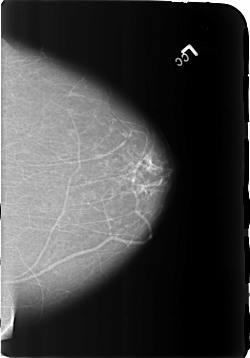

B_3172_1.LEFT_CC

LEFT_CC LINES 5728 PIXELS_PER_LINE 3992 BITS_PER_PIXEL 12 RESOLUTION 50 NON_OVERLAY

FILE: B_3172_1.RIGHT_CC.OVERLAY

TOTAL_ABNORMALITIES 1

ABNORMALITY 1

LESION_TYPE MASS SHAPE OVAL-LYMPH_NODE MARGINS CIRCUMSCRIBED

ASSESSMENT 2

SUBTLETY 4

PATHOLOGY BENIGN_WITHOUT_CALLBACK

TOTAL_OUTLINES 1

BOUNDARY